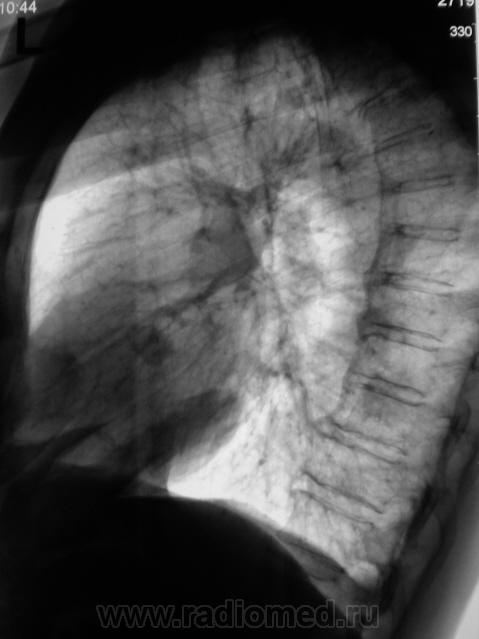

Контроль после флюорографии. Стандартное дообследование.

Ваше мнение уважаемые коллеги?

Mts? Но откуда? Что в анамнезе?